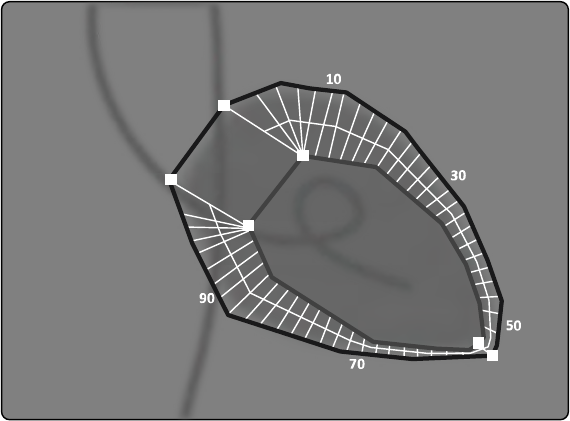

16.21.2 Mapy izokermy systemu C12/F12........................................................................ 310

16.21.3 Mapy izokermy systemu F15................................................................................ 311

16.21.4 Mapy izokermy systemu C20/F20........................................................................ 312